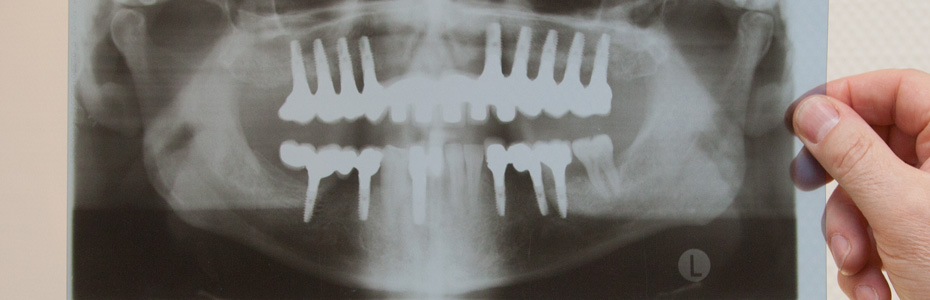

Implants may offer an aesthetic and permanent solution, even for people who are missing all of their teeth. When considering comfort and quality of life, removable prosthetics affixed to permanently anchored implants are clearly the optimal choice. Patients considering implants who do not have any teeth have two options: a fixed row of integrated teeth that is permanently affixed to implants, or a removable version that can be screwed on and off. The removable teeth do not slip or resist pressure but remain fixed to their implants. This treatment option offers a high level of comfort and a natural appearance. Patients who have been forced to cope with traditional dentures that slip, resist pressure, and cause pain when chewing, are delighted to enjoy the superior advantage that either implant option provides.